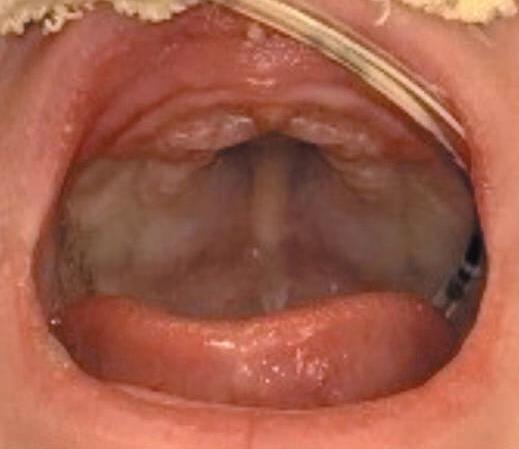

1-8. (a) Pré-operatória e (b) pós-retirada de dispositivo de expansão rápida de maxila à direita.

9. Ao final da expansão, nova TC pode ser realizada para mensuração objetiva do ganho de espaço aéreo (Fig. 1-4), além da avaliação clínica (Fig. 1-8).

Apesar da eficácia da técnica de desgaste ósseo na abertura piriforme, seus potenciais riscos e complicações levaram ao aparecimento de outras opções terapêuticas. Vários estudos demonstraram que a atresia é maxilar, não se limitando ao piriforme, mas se estendendo por quase toda a cavidade óssea nasal.12,14 A expansão rápida da maxila, com dispositivo disjuntor e ancoragem esquelética por meio de miniparafusos, com sua fundamentação anatômica, biomecânica e funcional, é menos invasiva, proporciona uma expansão tridimensional eficaz ao longo de toda a fossa nasal, produzindo uma melhora funcional consistente nas vias aéreas superiores, que se mantém ao longo de todo o período de crescimento craniofacial (Fig. 1-9). Assim, a ERM credencia-se como técnica de escolha no tratamento da ECAP.15